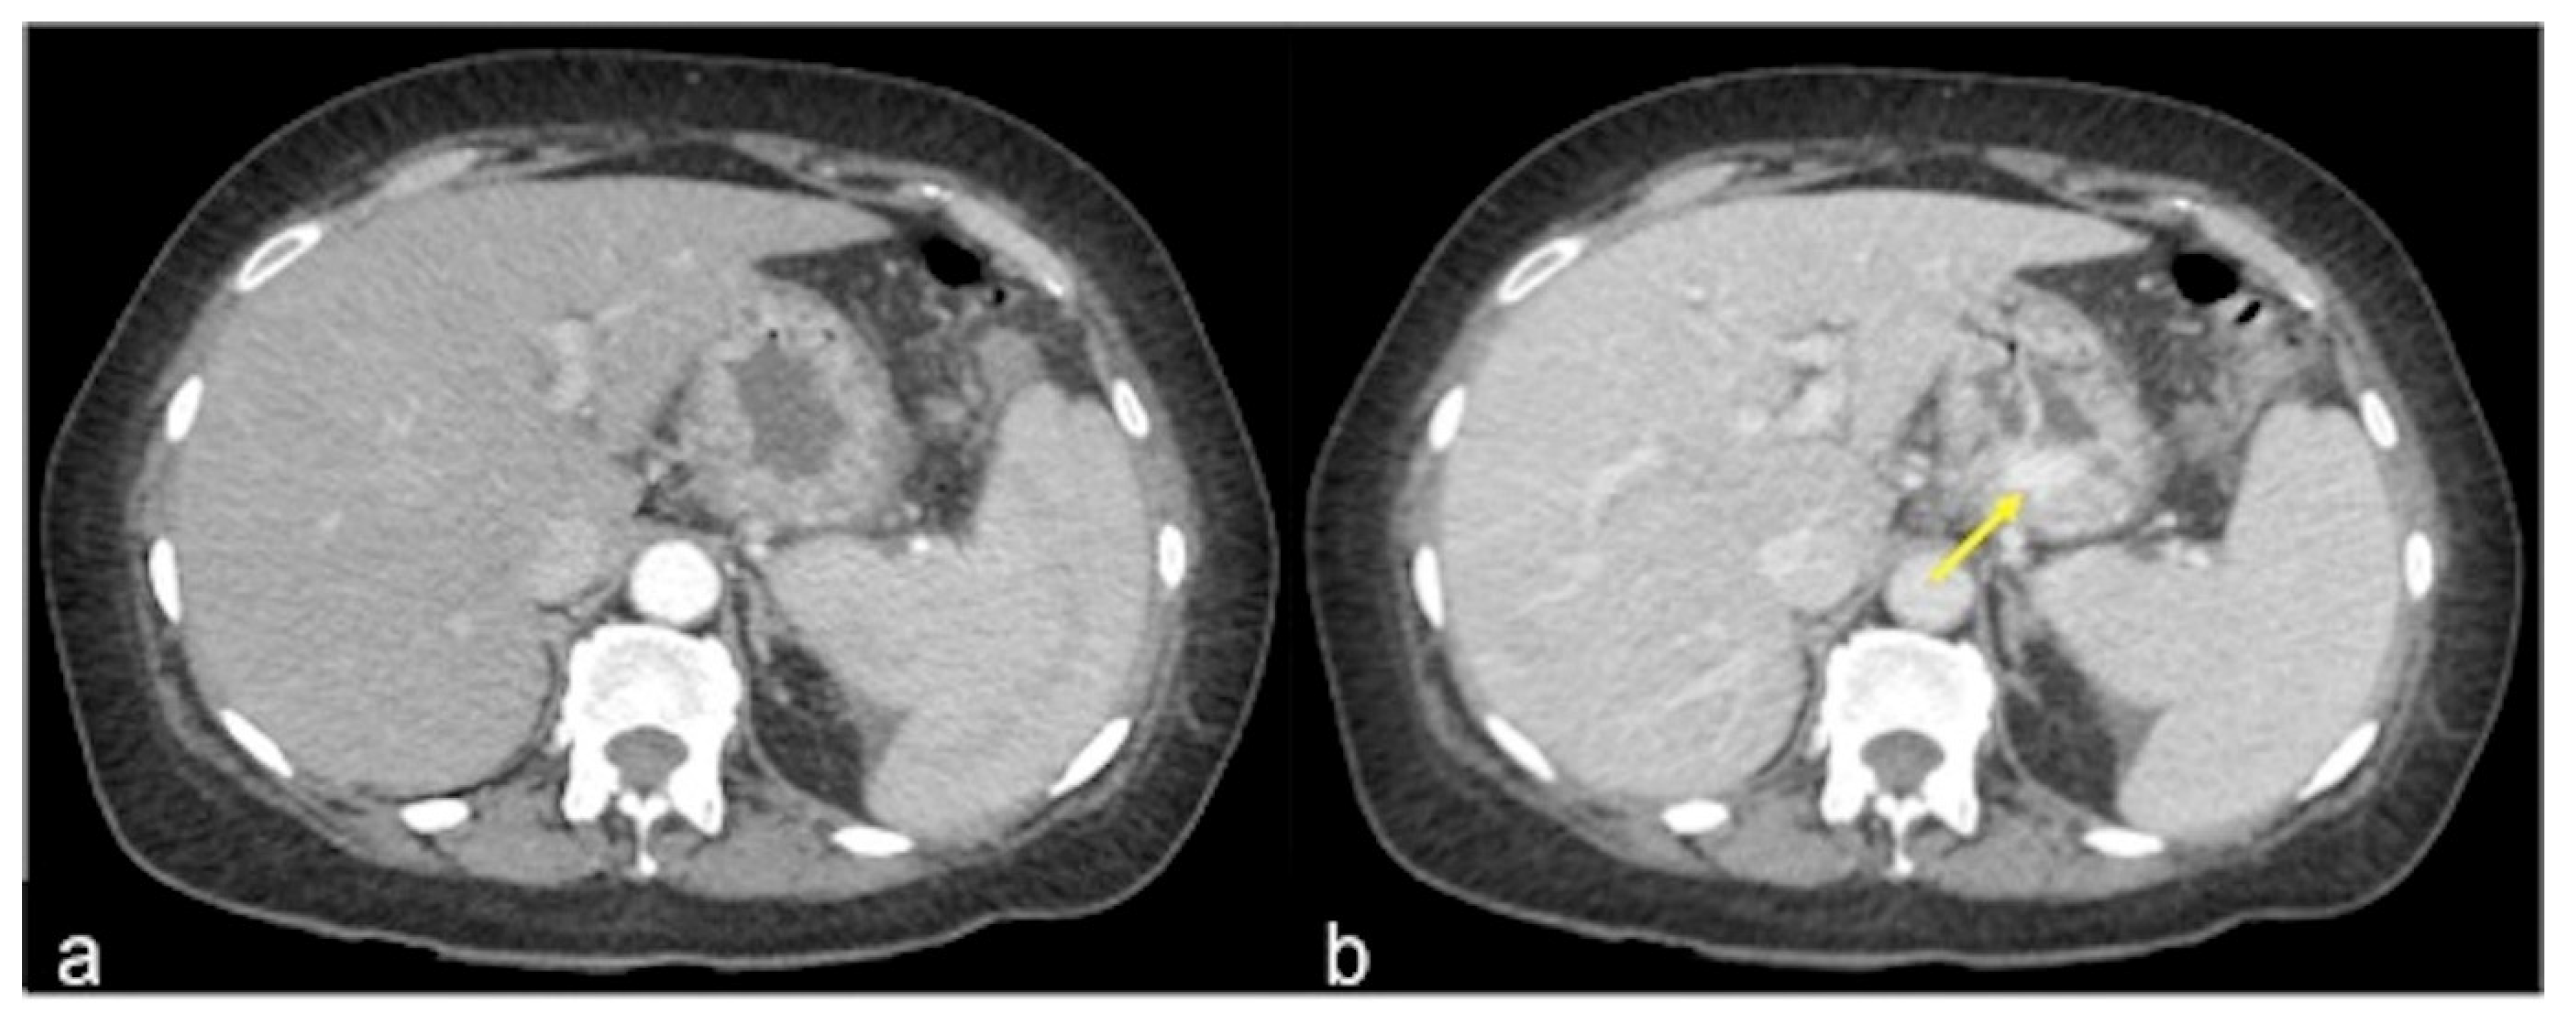

| Haemobilia (Figure 32) | Melaena, haematemesis, biliary colic, jaundice, or massive bleeding in a patient with a history of blunt or iatrogenic abdominal trauma. | Presence of blood in the gallbladder and biliary tree. |